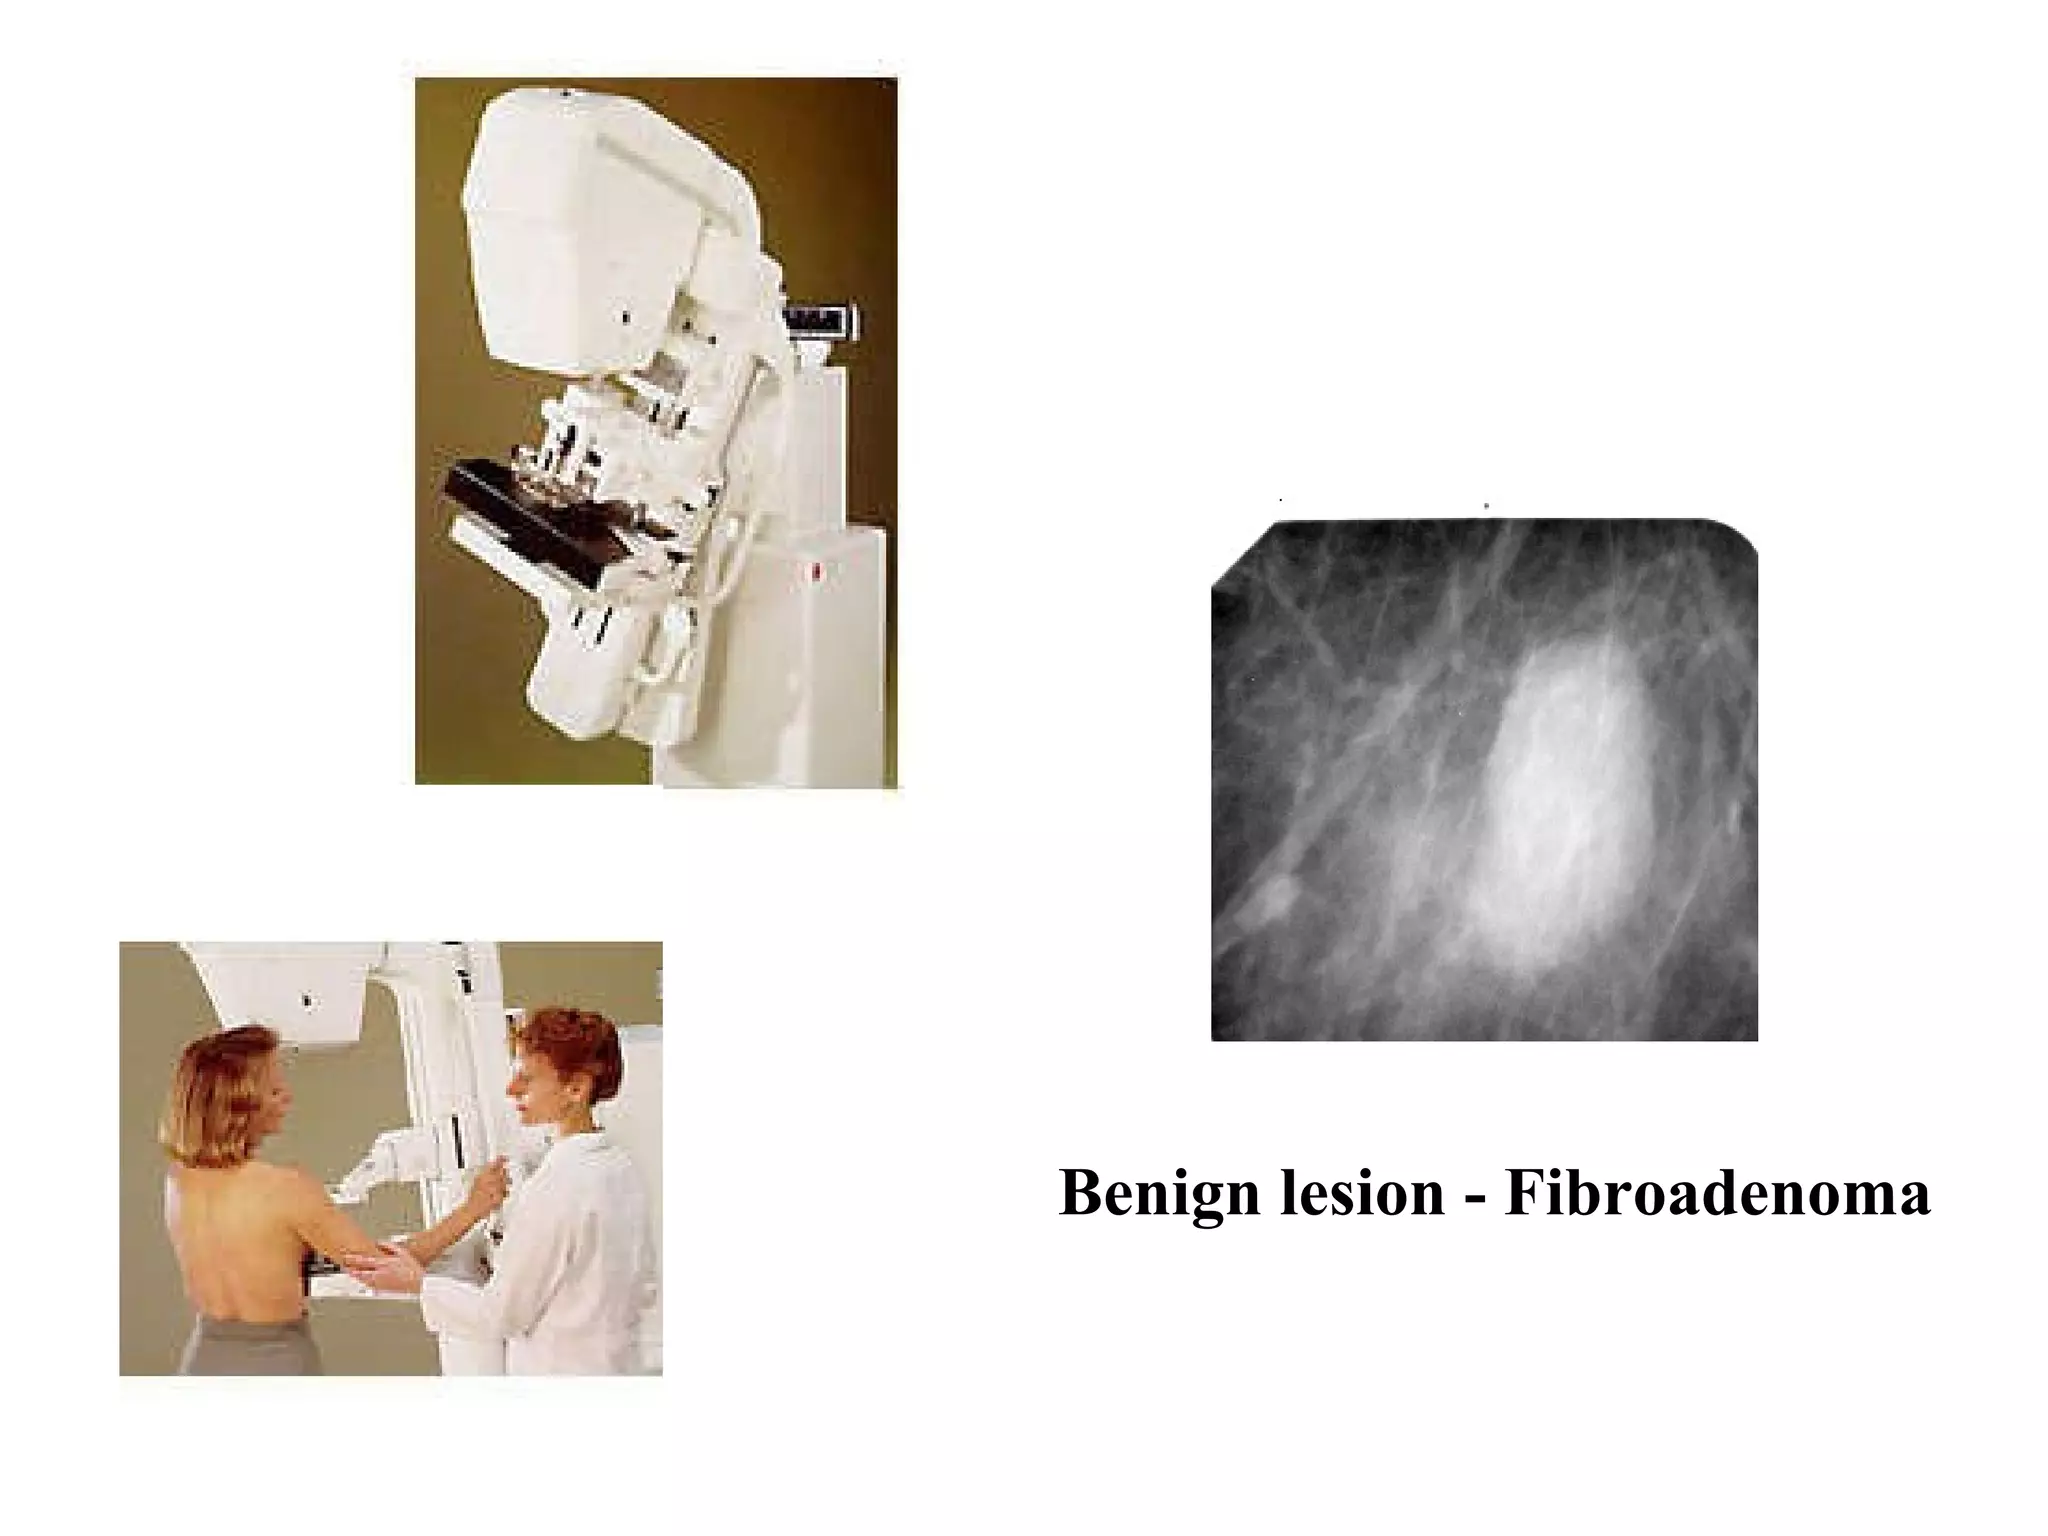

The document discusses various medical imaging modalities including x-rays, computed tomography (CT), and digital mammography. It describes the basic principles and historical development of these technologies, how images are formed, and what types of anatomical features and abnormalities they can detect. Key advances include the development of digital systems that allow image manipulation and remote consultation. While promising, digital mammography still faces challenges around resolution and cost.